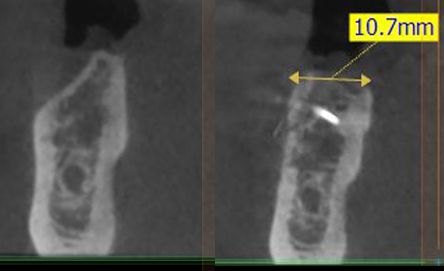

14/28 - Sagittal section of the alveolar ridge in the region of the defect before the augmentation and after 5 months of healing at implantationThree-dimensional augmentation with maxgraft® cortico - Dr. R. Würdinger